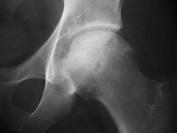

问题 女,60岁,髋部疼痛、活动受限、跛行,请结合图片像,选出最可能的诊断 ( )

选项 A、退变性囊肿 B、暂时性骨质疏松 C、髋关节结核 D、股骨头缺血坏死 E、骨岛

答案 D